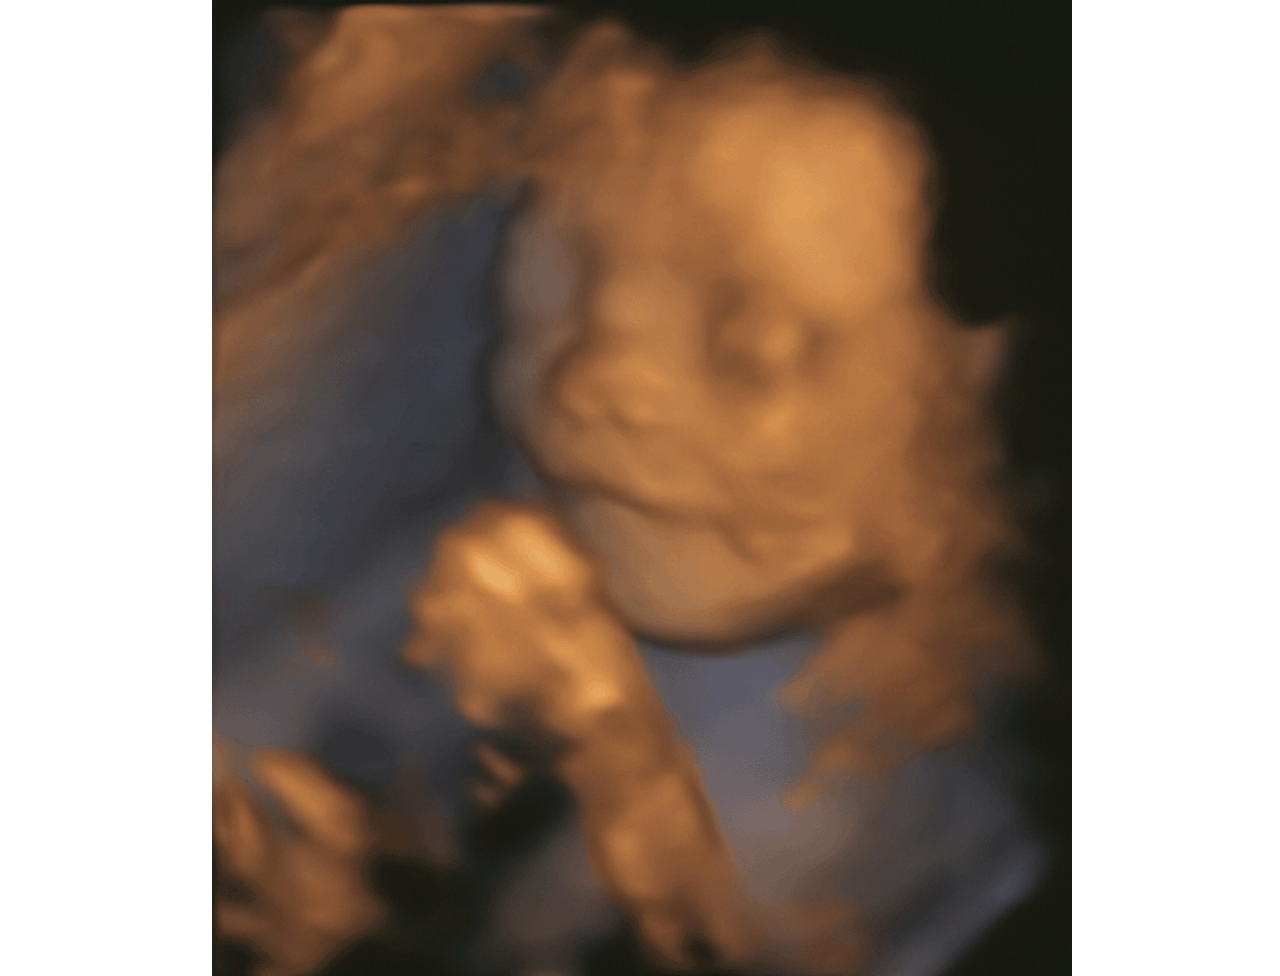

艾玛高品质服务 本文已为 位患者解决了问题 点击了解详情济南做四维彩超有哪些优势?现在怀孕的准妈妈们都要去做B超,从而了解宝宝的发育情况、是否有畸形等等等,现在不仅仅有二维三维四维,那么济南做四维彩超有哪些优势?就让济南艾玛妇产医院的医生来介绍下。

1.动态图像:所显示出来的不仅仅是宝宝实时活动的图像,而且还有内脏器官的实时图像。

4.体表检查:像些唇裂,脊柱裂,或者身体内部的肾、心脏等等,及时的发现有没有不规则的存在,以便尽早的进行治疗。